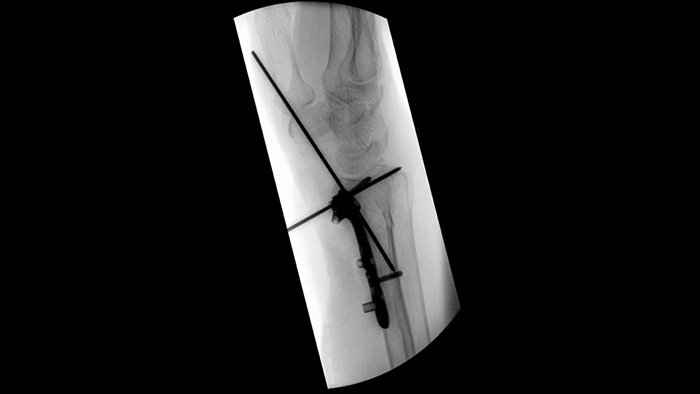

При установке транспедикулярных винтов для сращения позвонков или операций при переломах важно не отвлекаться на решение технических вопросов и обсуждения, персоналу необходимо полностью сосредоточиться на пациенте. Исследование удобства эксплуатации показало, что с помощью навигационных средств рабочего процесса Unify члены хирургических бригад смогли достичь более высокого уровня взаимодействия и координации1.

Упростите рабочий процесс для сложных ортопедических операций, требующих частой смены положения мобильной С-дуги. Благодаря функции Position Memory 2 участника исследования удобства эксплуатации1 смогли с первого раза сменить положение с точностью в 94% и испытали меньше разочарований при выполнении (повторного) позиционирования.